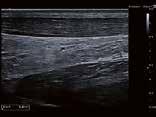

Thorax-CT im Rahmen einer Lungenkrebsfrüherkennungsstudie. Die Voruntersuchung lag als externe kontrastmittelgestützte Thorax-CT vor. Bei der dosisoptimierten Low-Dose-CT liegt die Strahlenexposition nur noch im Bereich von zwei konventionellen Röntgenaufnahmen des Thorax, die Bildqualität ist für die Fragestellung nach Herdbefunden aber dennoch eindeutig ausreichend, selbst interstitielle Lungenveränderungen lassen sich hier noch beurteilen.

Prof. Dr. med. Johannes Weßling Zentrum für Radiologie, Neuroradiologie und Nuklearmedizin Abb. 3 a: kontrastmittelgestützte Thorax-CT, externe Untersuchung; DLP 216,0 mGy × cm / 3,9 mSv. Abb. 3 b: dosisoptimierte Low-Dose-Thorax-CT, Canon Aquilion Prime SP, Rekonstruktion: AiCE; DLP 13,9 mGy × cm / 0,25 mSv.